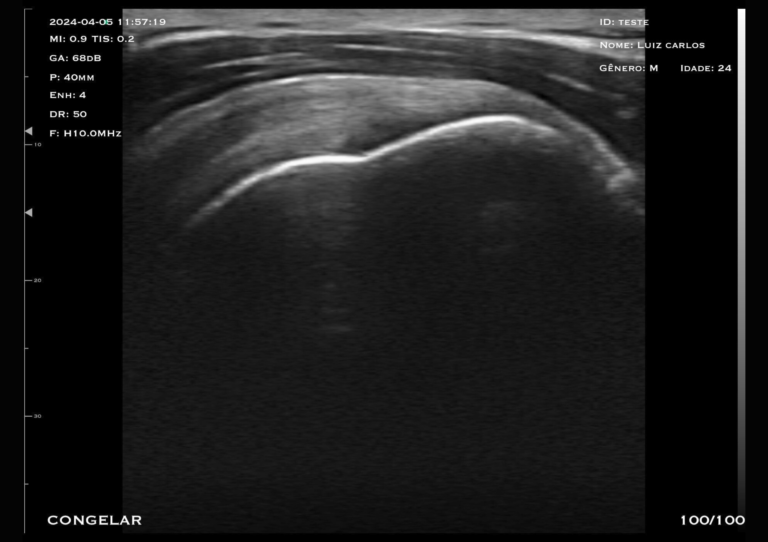

Com tecnologia linear e frequência de 7,5 a 10 MHz, o modelo M2HD é a escolha ideal para quem busca alta resolução em exames superficiais e intermediários, com foco em versatilidade e precisão sem a necessidade do doppler.

O transdutor linear oferece imagens nítidas e detalhadas, permitindo a visualização precisa de estruturas como mama, tendões, músculos e articulações.

A frequência ajustável garante versatilidade para diferentes tipos de exames, desde avaliações mastológicas até procedimentos ortopédicos.

Profundidade:

Linear (0 - 55 mm)